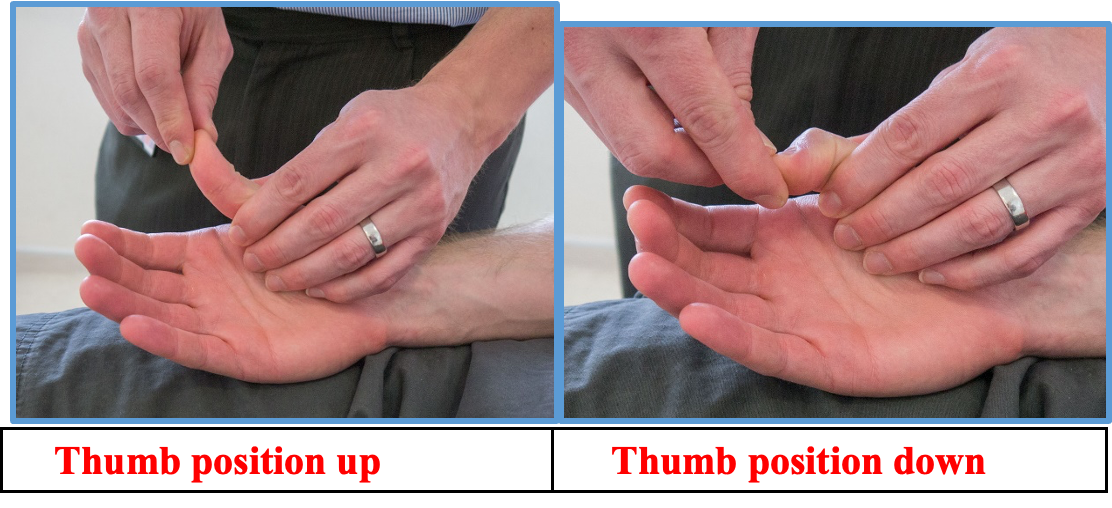

UL Proprioception joint position

Proprioception

-

Assess proprioception Hold the distal phalanx of the thumb on either side so that you can flex the interphalangeal joint.

-

Show the patient that when you hold the joint extended, that represents Up whereas when you hold it flexed that represents Down. Ask the patient to close their eyes and, having moved the joint a few times hold it in one position – up or down. Ask the patient which position the joint is in.

Lower limb proprioception JPS

Proprioception Hold the distal phalanx of the great toe on either side so that you can flex the interphalangeal joint. Show the patient that when you hold the joint extended, that represents Up whereas when you hold it flexed that represents Down. Ask the patient to close their eyes and, having moved the joint a few times hold it in one position – up or down. Ask the patient which position the joint is in.